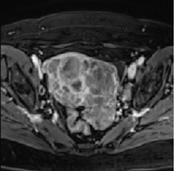

Functional imaging for individualised cancer treatment (Professor Ingfrid Haldorsen).

The research group aims to:

- Explore functional imaging findings i.e. potential imaging biomarkers that predict advanced tumor stage, lymph node metastases and reduced survival in patients with uterine cancers.

- Validate and compare these imaging biomarkers with established histomorphological and molecular biomarkers in uterine cancers.

- Implement these imaging biomarkers in the preoperative risk stratification to enable better tailored and individualized treatment of uterine cancers.

- Explore functional imaging findings in an orthotopic animal model of primary and metastatic lesions of uterine cancers.

- Explore imaging characteristics as tools to detect early drug response in orthotopic tumour grafts.